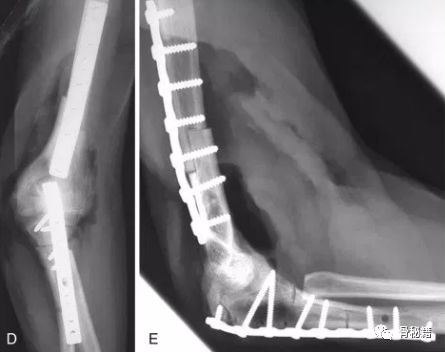

该例患者的前倾角就没有较好的恢复

3.术中如何保证恢复呢和判断呢?

在肱骨前方画一条线,看看该线的位置,是否经过滑车的中心,如果经过则说明复位较好。